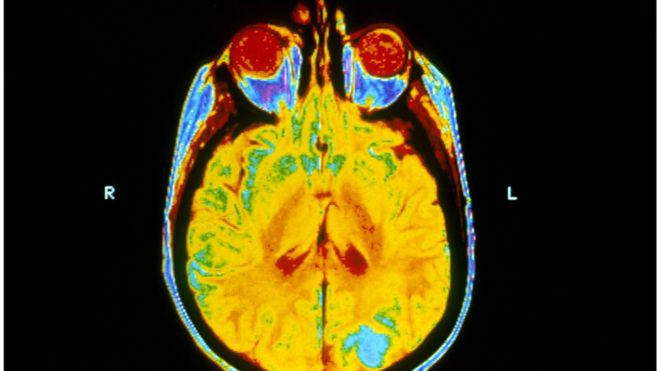

Xạ trị não bộ không giúp chữa trị căn bệnh ung thư phổi di căn

Theo kết quả nghiên cứu vừa được đăng trên tạp chí y học The Lancet, xạ trị não bộ không đem lại lợi ích gì cho các bệnh nhân ung thư phổi di căn lên não.

Các khối u não thứ cấp thường được điều trị bằng xạ trị toàn bộ não cùng với steroid và các phương pháp điều trị khác để giảm tác dụng phụ của phương pháp điều trị ung thư. Tuy nhiên, nó cũng có tác dụng phụ nghiêm trọng, gây buồn nôn, mệt mỏi, và tổn hại cho hệ thần kinh.